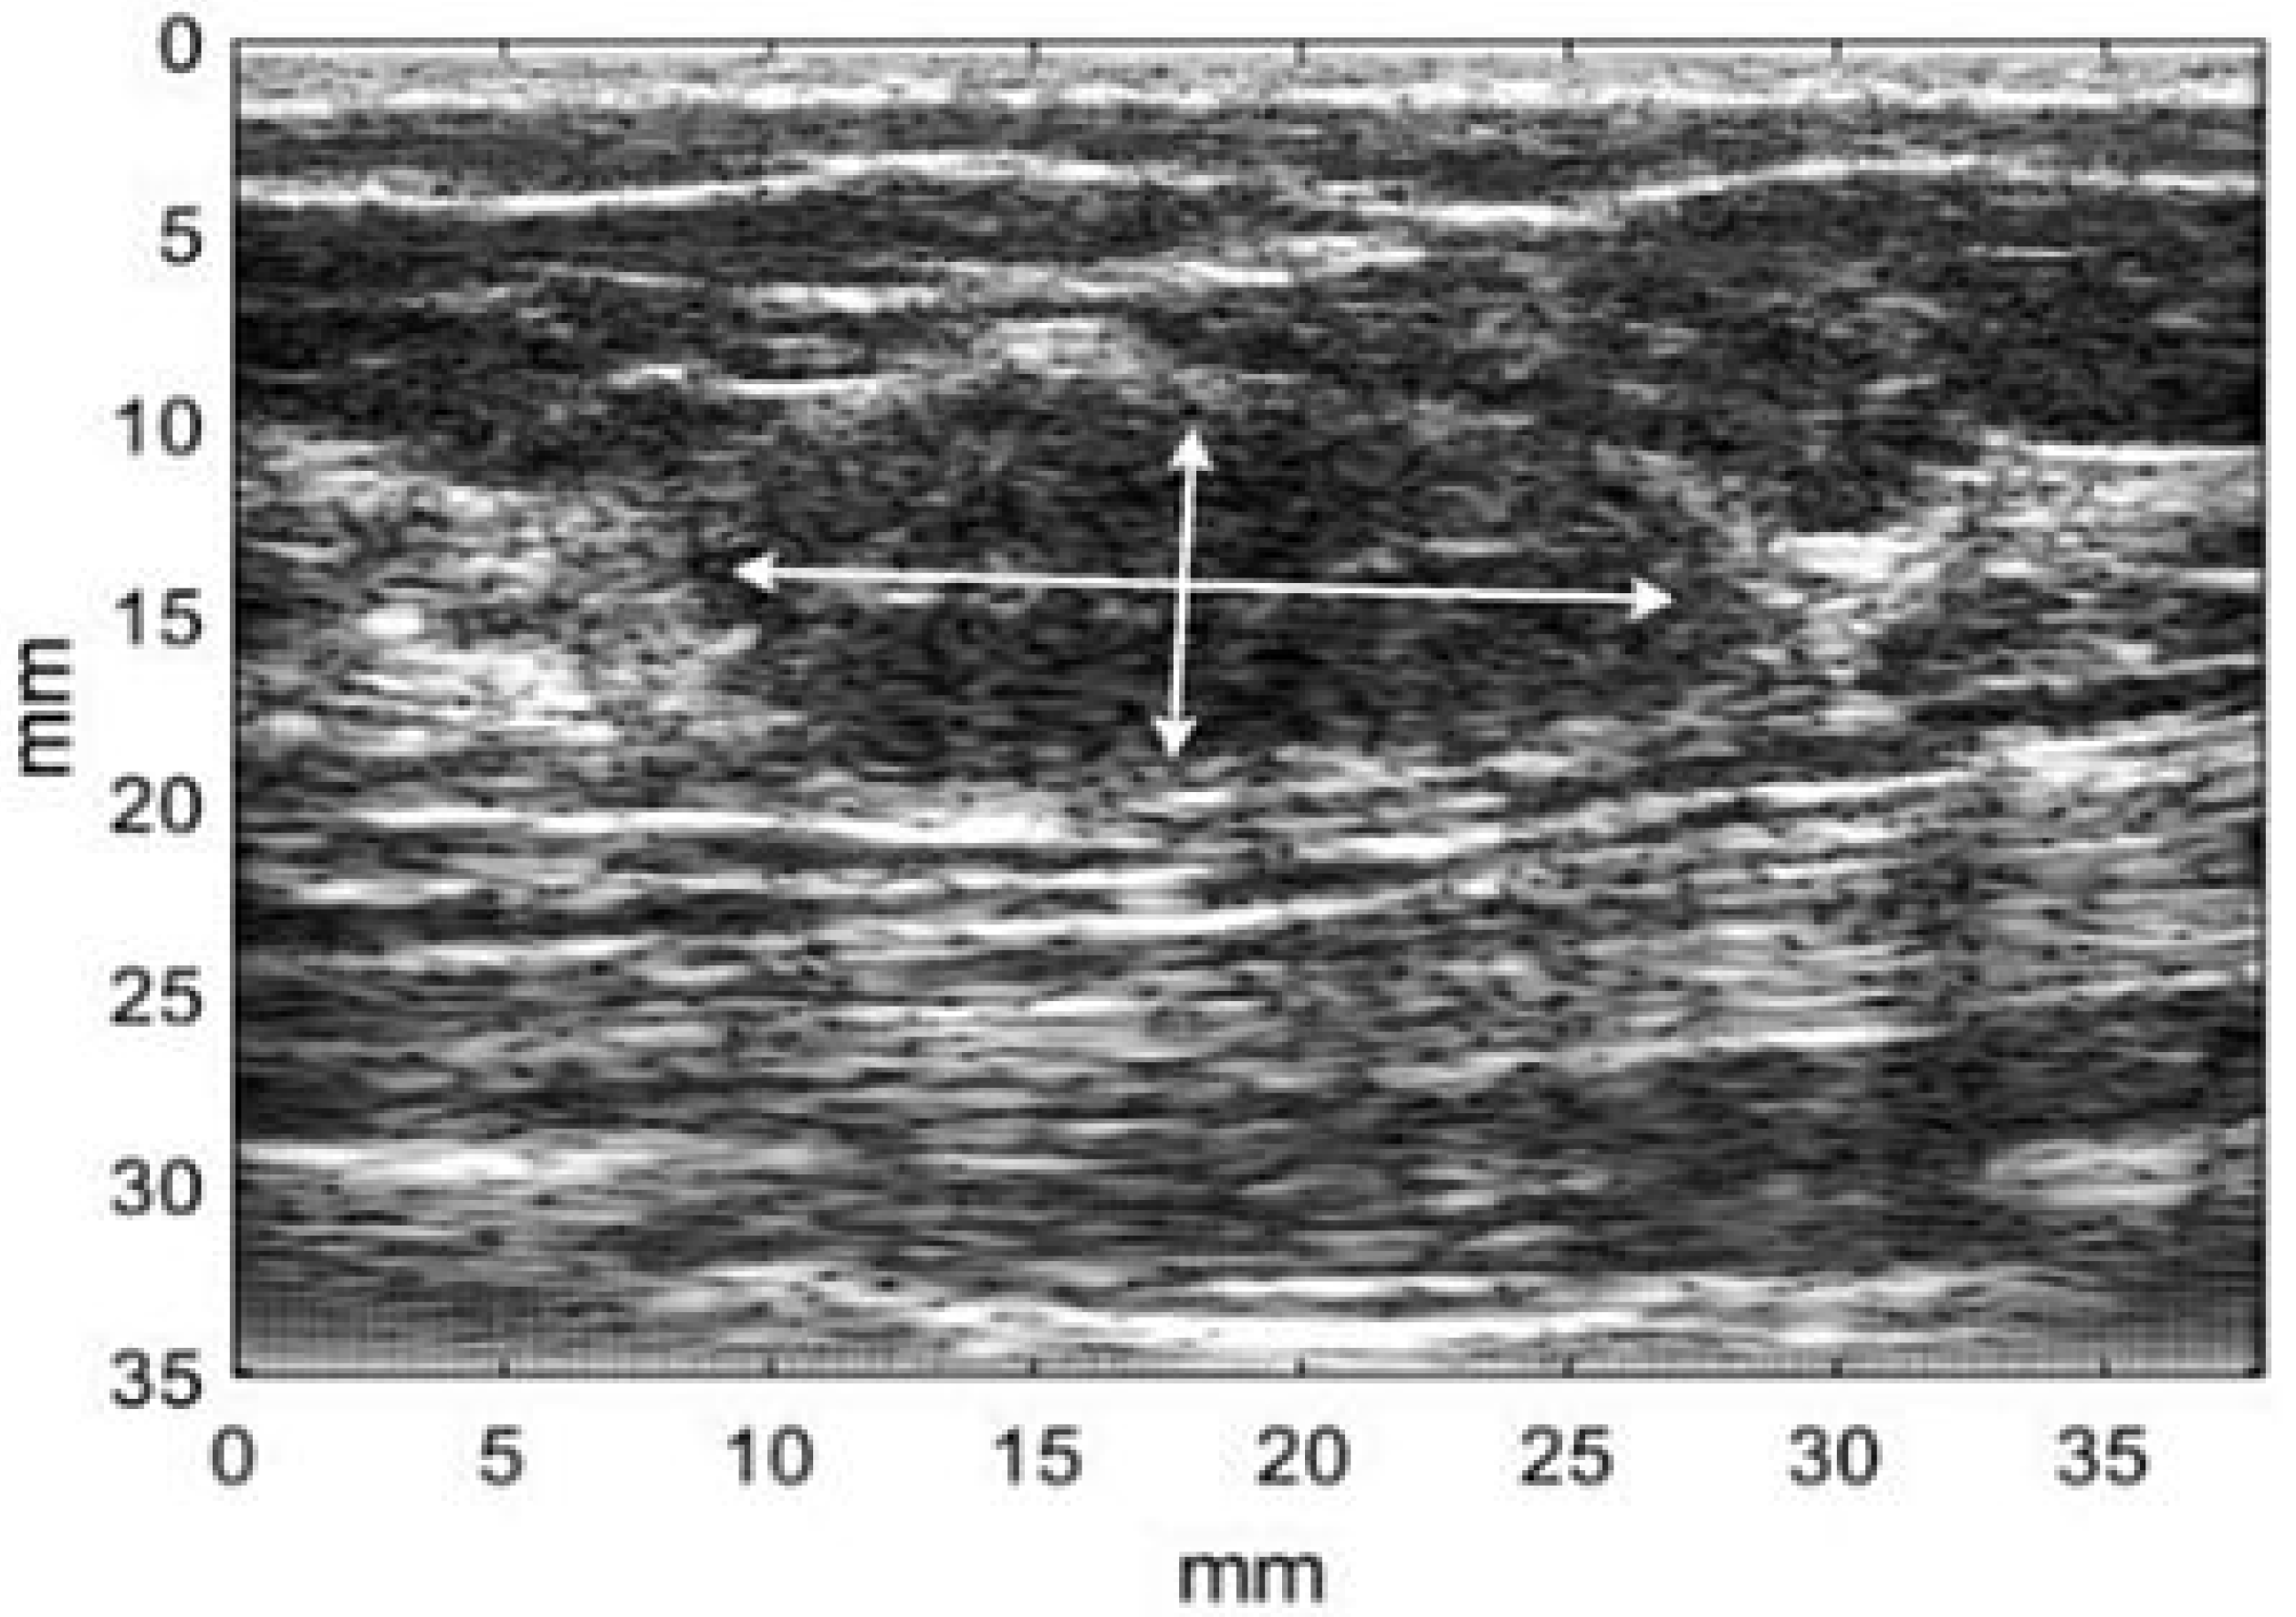

2.1. Image Database

- Gomez, W.; Leija, L.; Alvarenga, A.V.; Infantosi, A.F.C.; Pereira, W.C.A. Computerized lesion segmentation of breast ultrasound based on marker-controlled watershed transformation. Med. Phys. 2010, 37, 82–95. [Google Scholar] [PubMed]